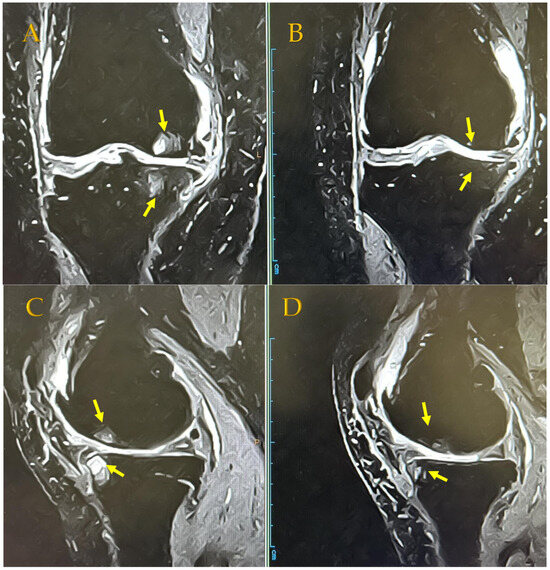

In addition, combined treatment may be expected to produce anti-inflammatory and cell proliferation effects, as seen on radiographs of the KL4 front-of-knee OA of a 64-year-old woman before APS therapy and 48 months after APS therapy. This patient continued ESWT approximately once or twice a month after the APS injection but showed a slight opening of the joint dehiscence compared with that before the APS injection (Figure 4). MRI of the same patient 48 months later showed the reduction in BML in T1 (upper photo), and the disappearance of bone cysts in T2 (lower photo) was confirmed (Figure 5). Since APS is a PRP product, it originally contains a large amount of TGFβ; however, the increased TGFβ level due to ESWT stimulation may have contributed to the anti-inflammatory effect and the regulation of cell proliferation and differentiation [,].

MRI findings of a KL4 64-year-old female patient. (A) BML and SBC on medial condyle Pre-APS therapy. (B) In T1 (upper photo), MRI after 4 years confirmed a reduction in BML, and in T2 (lower photo), the disappearance of bone cysts was confirmed. 8 October 2019 MRI T1 Pre-APS therapy (lt.) → 16 October 2023 MRI T1 4 years later after APS therapy (rt.); APS (31 October 2019) + ESWT 36 times (every 1–2 months) after APS therapy. (A) coronal view (18 October 2019) (B) coronal view (16 October 2023) (C) sagittal view (18 October 2019) (D) sagittal view (16 October 2023).